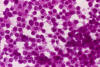

2. Hematoxylin and eosin stain, squash cytologic preparation

Note the cytoplasmic vacuoles (arrow). Glycogen does not take up eosin stains.

First, although it is composed of small blue cells, the nuclei are marginally larger than other small blue cell tumors such as small cell carcinoma or medulloblastoma. Their nuclei are also slightly less crumbled after fixation, less hyperchromatic, and have slightly more open chromatin. A small nucleolus can be seen in many nuclei. The nuclei seems to be more monotonous on cytologic (squash or touch preparation) and crush effects on nuclei (smearing of nuclei) is far less common than other small blue cell tumors. Histologically, it is not uncommon for Ewing's sarcoma to have areas of more densely packed areas with hyperchromatic nuclei and these areas are embedded within a slightly less densely packed area with more open nuclei (Image 1 below). On cytologic preparations, small vacuoles may be present in the cytoplasm. These vacuoles are glycogen granues which could be partially washed out during processing as glycogen has a low aqueous solubility and are typically not entirely washed out during processing (arrow in image 2 below).  These vacuoles can be seen in both hematoxylin and eosin stained and Diff-Quick stained cytologic preparations but Diff-Quick works better [Click here to see a case]. Together with the appropriate clinical information, these histologic features are highly suggestive of Ewing's sarcoma.

Tumor cells are fairly uniform and have a small amount of cytoplasm typically in the form of a thin rim. Intercellular gaps that are often seen in hematopoietic neoplasms may be present. Cytoplasmic vacuoles corresponding to the glycogen vacuoles can be well appreciated in cytologic preparations. However, it is hard to differentiate them from fixation artifacts in permanent sections. Ewing sarcoma typically contains a good amount of glycogen that are well demonstrated by PAS stain with and without diastase pre-digestion. The nuclear chromatin is finely granular. Although it is a small round cell tumor, its nuclei tend to be marginally larger and less crumbled than many of the other small round cell tumors such as small cell carcinoma. It is common to have geographic patches of cells with open chromatin alternating with areas with closed chromatin leading to a biphasic dark cells and light cells pattern. Small but identifiable small to moderately sized nucleoli. Large and prominent nucleoli can be seen in large cell Ewing sarcoma. Otherwise, large and prominent nucleoli are not typical for Ewing sarcoma.